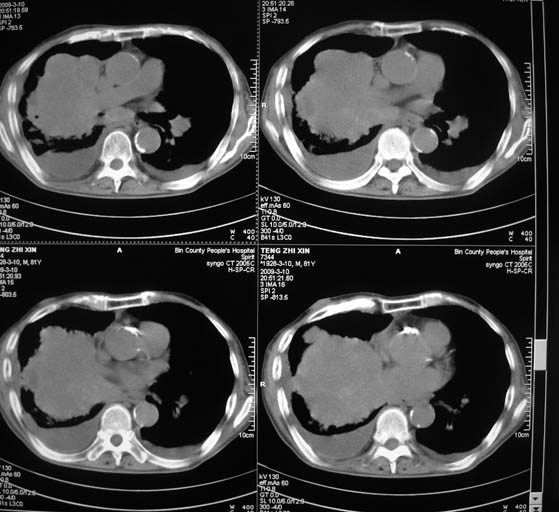

标题: CT18642:男,81岁,发热待查。

男,81岁,发热待查,右侧是占位还是膈疝?

右肺中央型肺癌并两侧胸水,左肺转移,腹水

右中央型肺癌并双肺及胸膜、肝脏转移

右中心型肺癌并双肺及胸膜、肝脏转移!

右肺中心型肺癌,胸、腹水